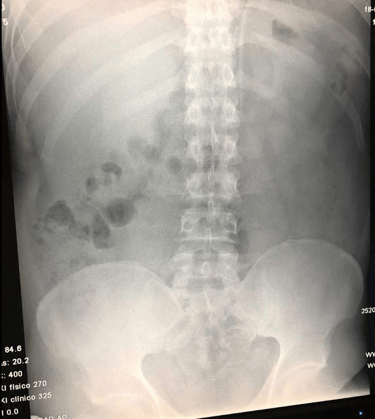

Si el dolor de espalda persiste, es importante acudir a un especialista para determinar su causa exacta. Algunos de los diagnósticos más comunes incluyen:

Si el dolor de espalda es persistente o interfiere con tu rutina diaria, es importante acudir con un especialista. A través de una evaluación clínica y estudios de imagen, se puede identificar la causa del problema y diseñar un tratamiento adecuado para aliviar el dolor de manera efectiva.